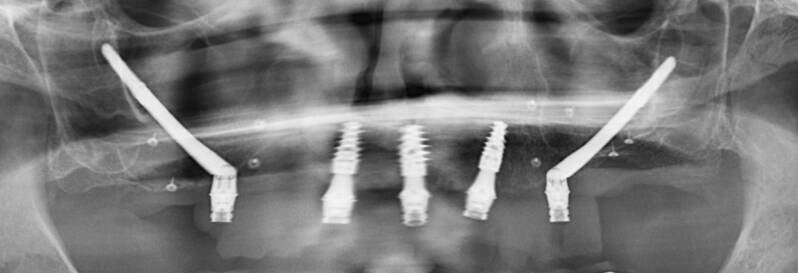

Rehabilitación de atrofias severas tanto maxilares como mandibulares mediante Implantes Cigomáticos e Implantes Personalizados Subperiósticos